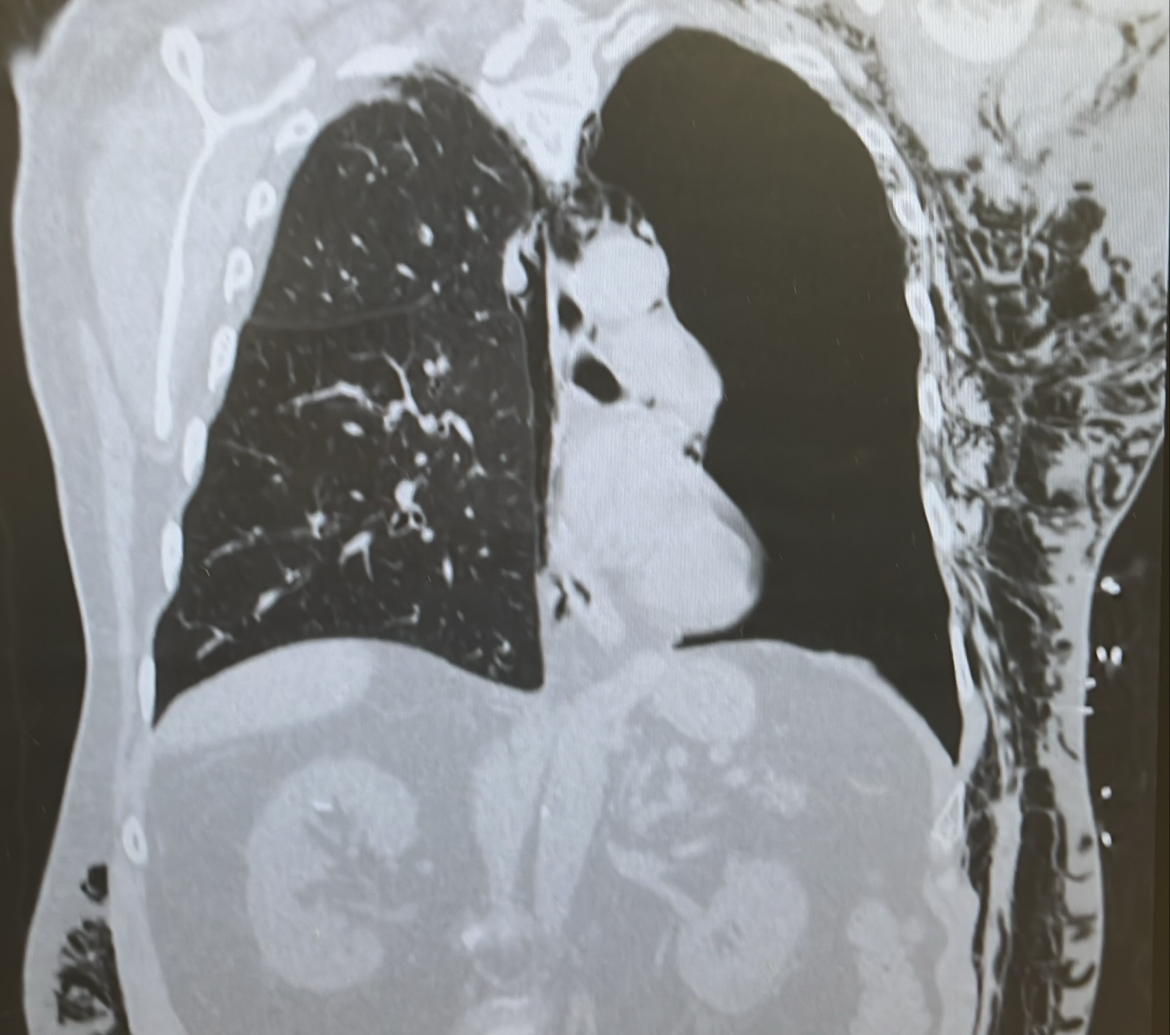

Critical Care Casebook Episode 4: Subcutaneous emphysema

Subcutaneous emphysema is typically benign and resolves on its own without the need for targeted therapy.

In rare instances, it can become extensive enough to threaten the airway. In these situations, small skin incisions (“blowholes”) may be created to facilitate the release of trapped air.

Management should also address the underlying pneumothorax, which generally requires placement of a new chest tube. When subcutaneous emphysema is severe, inserting a pigtail catheter may be technically challenging, and a traditional surgical chest tube may be more appropriate.

If there is concern for impending airway compromise, early intubation should be considered to secure and protect the airway. The use of a “blowhole” technique should be reserved as a last-resort intervention. The blowhole—an incision near the clavicle to release trapped air—is a temporary, last-resort maneuver described mainly in case reports. Definitive management means fixing the underlying lung or tracheal injury.